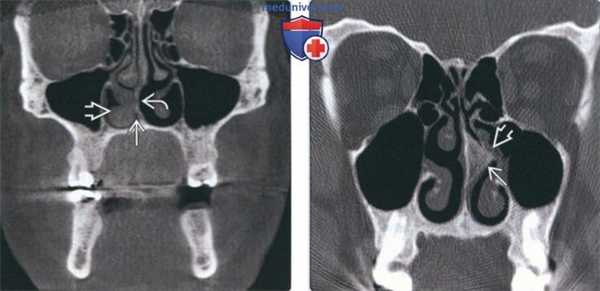

(Слева) На корональной КЛКТ определяется отклонение носовой перегородки влево, выраженное сужение просвета полости носа слева по сравнению с противоположной стороной.

(Справа) На аксиальной КЛКТ определяется отклонение носовой перегородки влево. Воздухоносные пути слева сужены по сравнению с противоположной стороной, но остаются проходимыми.